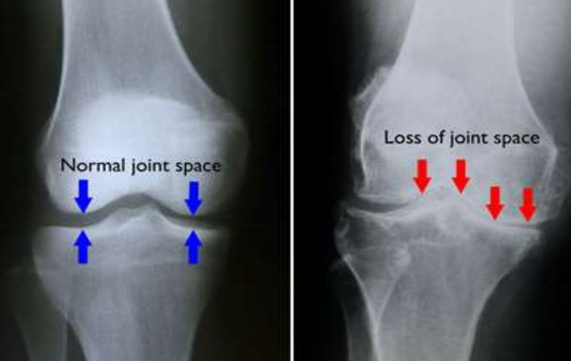

Knee osteoarthritis should NOT be diagnosed by using an x-ray in isolation. In fact, studies have shown that changes in a knee x-ray are an imprecise guide to whether or not the individual will have knee pain. Therefore, it is possible to show signs of osteoarthritis on an x-ray and to not have any pain or disability.

You should NOT consider getting surgery based entirely on your scan of the knee. There are many cases where severe changes on an x-ray are associated with only mild symptoms and moderate changes are associated with severe symptoms. Rather you should decide on whether or not you get surgery based on the following:

It is important that you realise that not everyone who has knee osteoarthritis requires surgeries and physiotherapy can be an equally effective means of treatment. You should not get surgery simply because an x-ray shows a loss of cartilage as it is possible to have this on a scan and experience no pain.